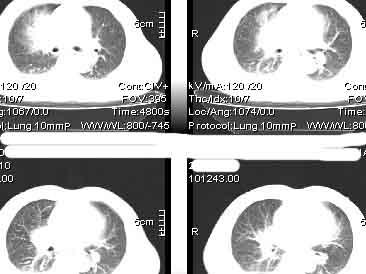

该病例我的诊断意见:右肺上叶周围型肺癌伴纵隔和右肺门淋巴结增大和右肺上叶阻塞性肺炎{病灶周围致密影以近肺门侧明显!}。右侧少量胸腔积液。

一. 1)症状有无发热及慢性过程.2)化验室检查?3)有无tb接触史?二.右肺上叶见片团状影,边界欠清,外侧方见一结节状软组织影,密度欠均匀,内可见低密度坏死区.周围强化明显,肺内见纤维索条影,局部胸膜增厚,但无明确胸膜凹陷.上叶支气管壁增厚,肺门及纵隔淋巴结增大.右侧胸腔少量积液.诊断意见:1右肺上叶慢性感染性疾病(肺tb?)伴肺门,纵隔淋巴结大.右胸少量积液.右肺上叶结节影多为tb球?2右肺上叶周围型肺ca伴肺门,纵隔淋巴结转移待排.右肺上叶炎变(肺门及纵隔淋巴结压迫).右胸少量积液.等待随返结果.

右上肺周围性肺癌,阻塞性肺炎考虑为肿大淋巴结压迫上叶支气管引起。